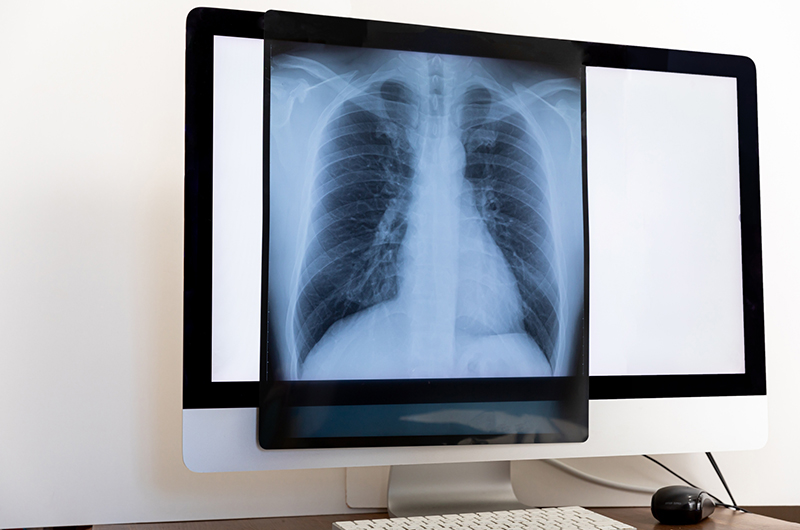

初期の肺がんは自覚症状がほとんどないことが多く、症状が現れた時にはある程度進行している場合があります。そのため、定期的な肺がん検診による早期発見が非常に重要です。胸のレントゲン検査やCT検査により、症状が出る前の小さながんを発見できる可能性があります。

- 胸のレントゲン検査

- 肺全体を撮影して、異常な影がないか調べます。